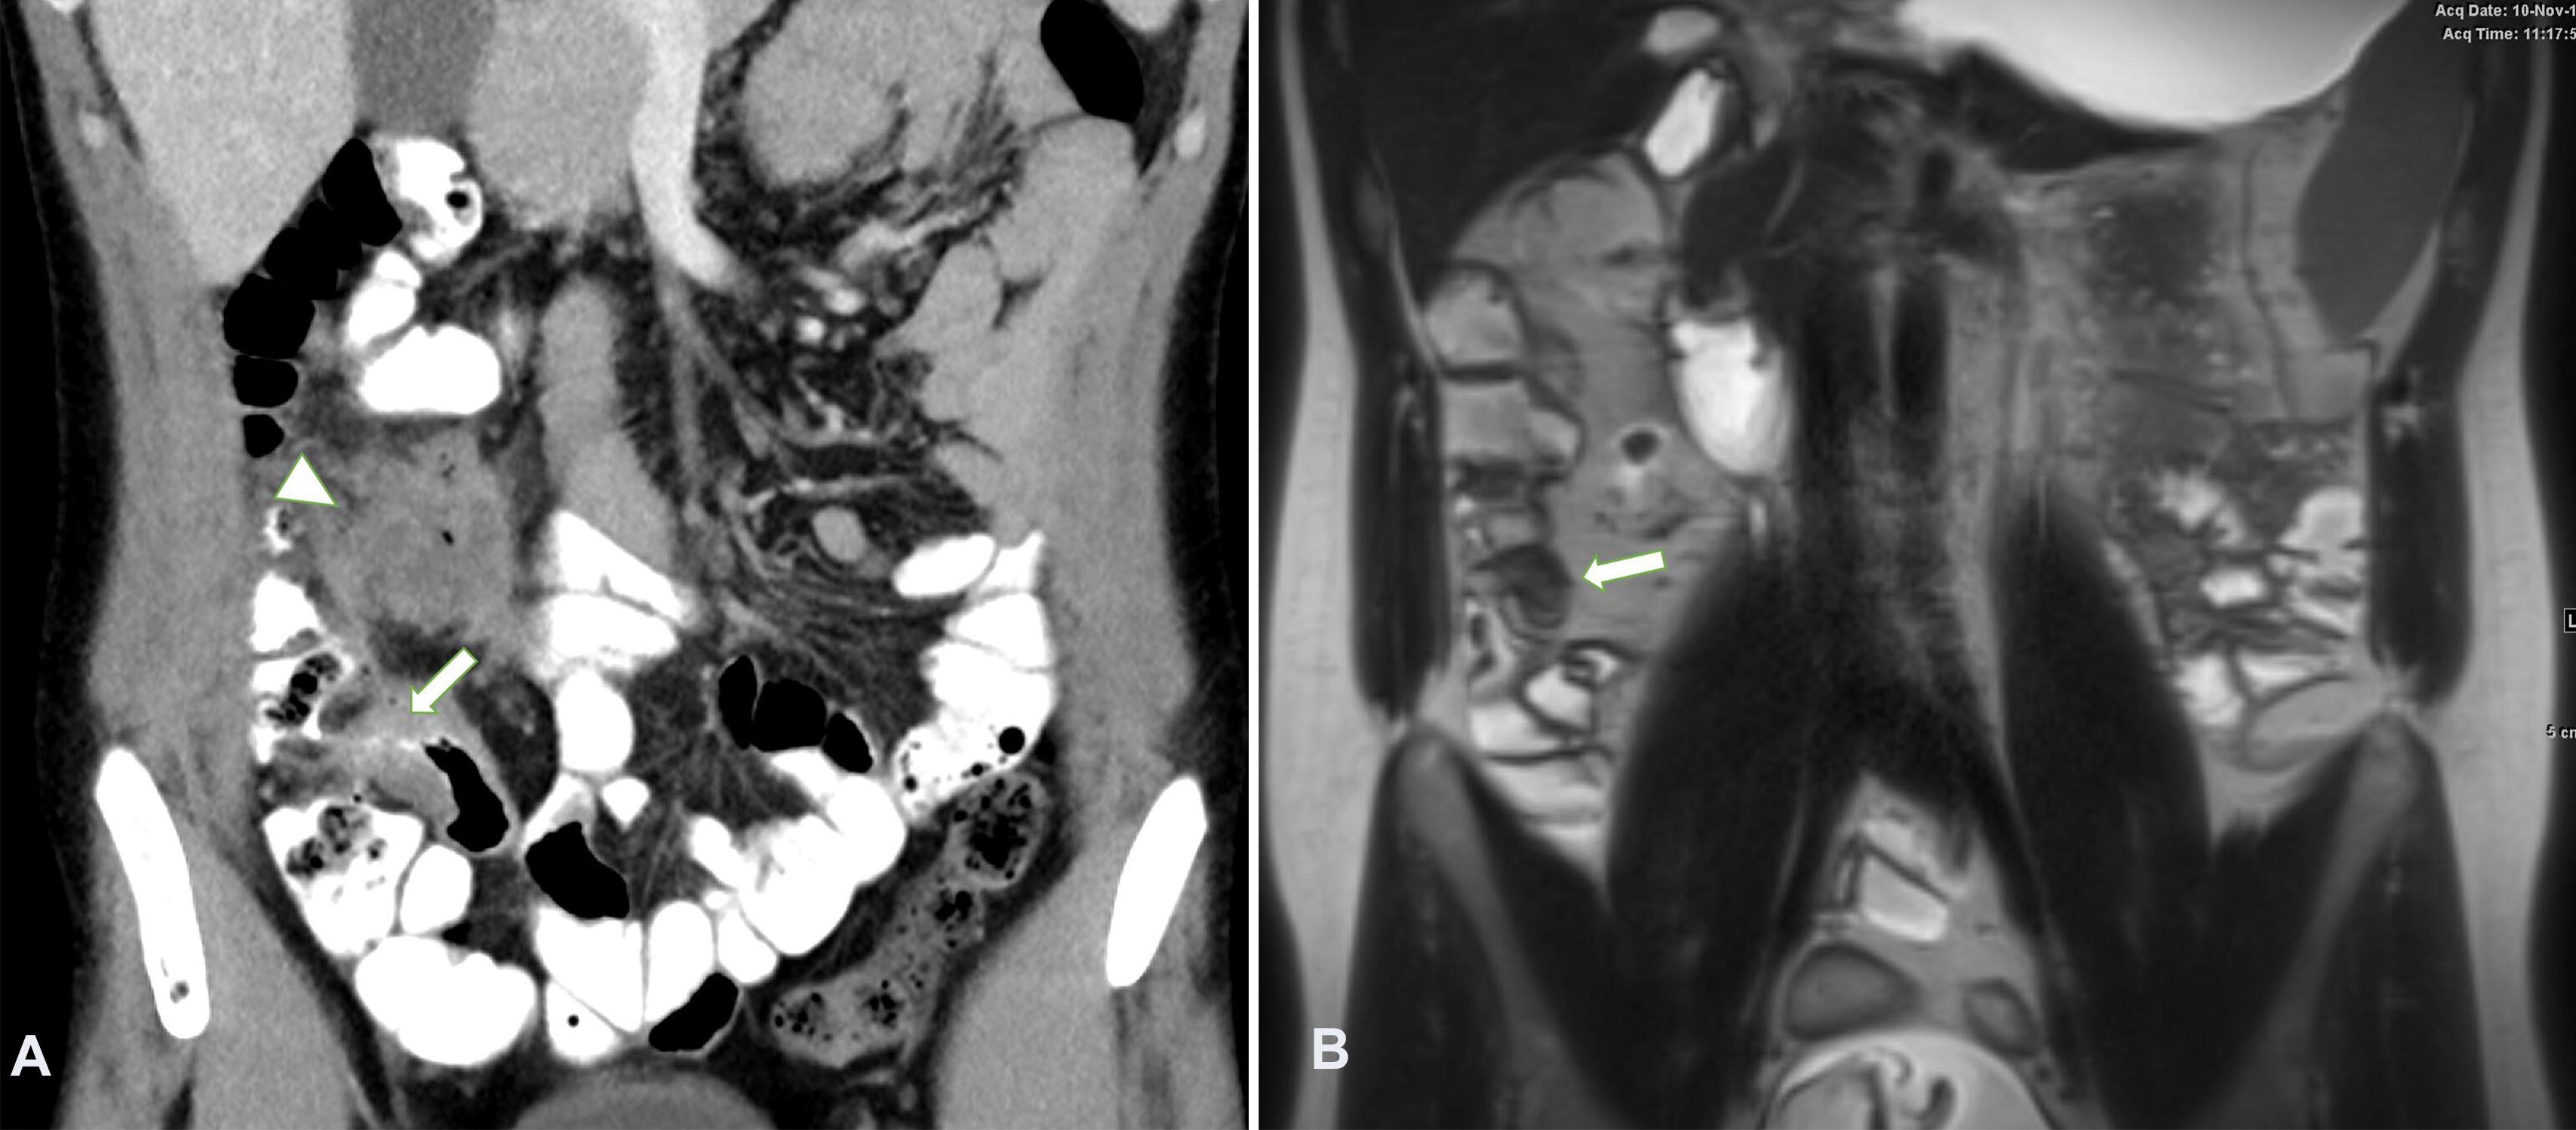

After a median follow up duration of 20 months (range: 3–210), all participants achieved clinical and biochemical improvement with conservative management however two participants ultimately underwent surgical resection (Table 2). The remaining nine participants were managed conservatively. Complete resolution of abscess on progress imaging was seen in 4/7 participants and a significant reduction in abscess size was seen in 2/7. One participant did not have progress imaging but there was clinical and biochemical resolution of sepsis. None of these participants underwent percutaneous drainage. Endoscopic and histological improvement was seen in all participants who underwent repeat endoscopy (N = 7). Two participants had complete endoscopic and histological remission as well as complete resolution of abscess on imaging (Figure 1 and Figure 2). Both participants with fistulising disease without a discreet collection had an excellent response to conservative management with progress MRE and colonoscopy which showed no evidence of an active fistula tract. In terms of reasons for undergoing surgery, one participant had recurrent intra-abdominal collections after initial conservative management (including percutaneous drainage) however his management was significantly compromised by poor adherence to medical therapy and follow up. The second participant re-presented with a large abscess after initial conservative management of a small collection. He underwent percutaneous drainage and medical optimisation before undergoing a right hemi-colectomy.

Figure 1

Figure 1. Thickening in the terminal ileum. A. Coronal CT with oral and IV contrast demonstrating thickening in the terminal ileum (white arrow) and an abscess superior to it (white arrowhead) from penetrating disease. B. MRI coronal T2 weighted sequence 2 years later demonstrating the thickening in the terminal ileum is significantly reduced (white arrow) and there is complete resolution of the previously demonstrated abscess. CT: computerized tomography; MRI: magnetic resonance imaging.